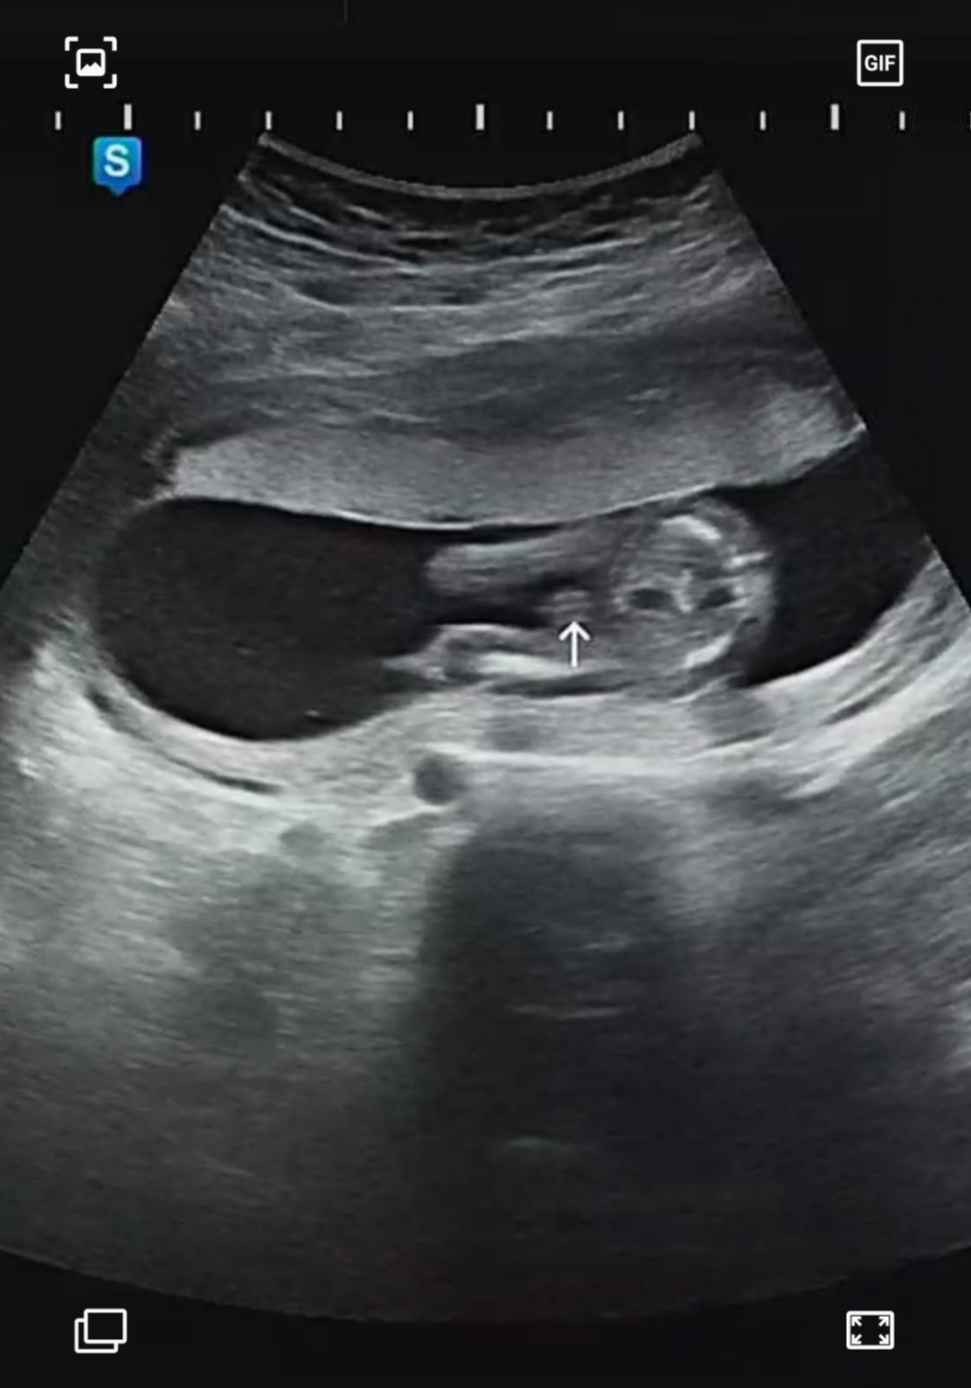

우리 까꿍이의 성별은 바로 꼬추이다😉!! 주기적으로 병원을 방문해서 까꿍이 성장하는 키를 봤을 때 항상 최대치를 찍길래 여아보다 상대적으로 큰 남아인가 보다 생각했는데,, 역시나였다. ㅎㅎ